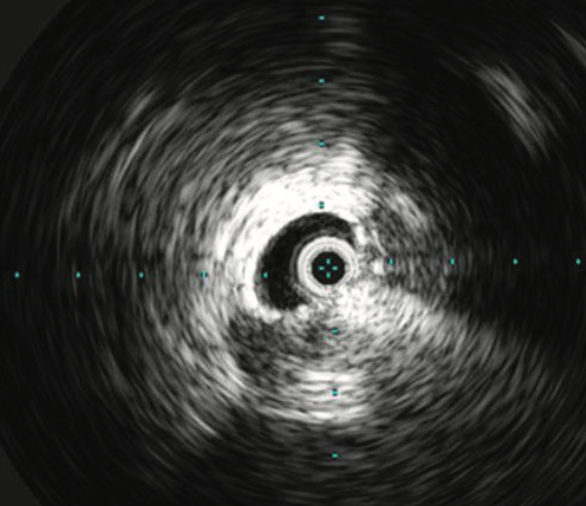

Corey K. Goldman, MD, PhD; Back Kim, MD; Tae An Choi, ANP-BC

In iliac vein compression syndrome, the overlying right iliac artery causes extrinsic compression of the left iliac vein in more than 80% of cases.